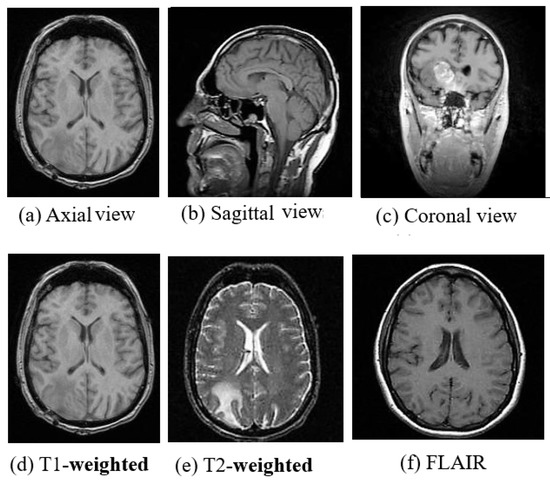

3.2. Magnetic Resonance Imaging

6.2.1. Input Image Format